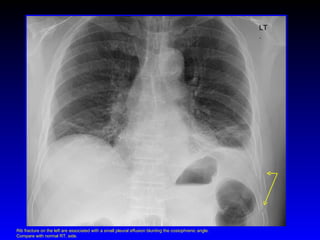

LT. Rib fracture on the left are associated with a small pleural effusion blunting the costophrenic angle. Compare with normal RT. side.

• #78 Rib fracture on the left are associated with a small pleural effusion blunting the costophrenic angle. Compare with normal RT. side.